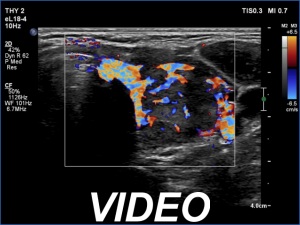

Left lobe, color Doppler mode